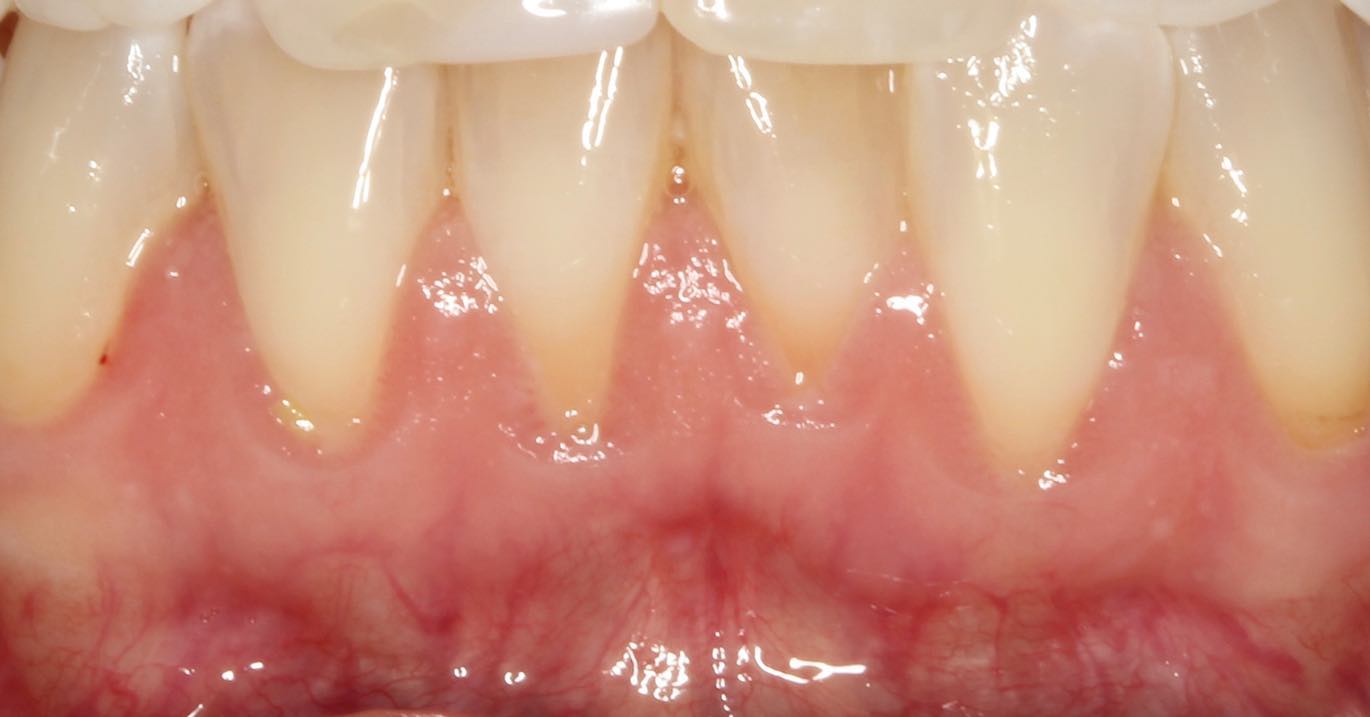

Connective Tissue Gingival Grafting for Gingival Recession